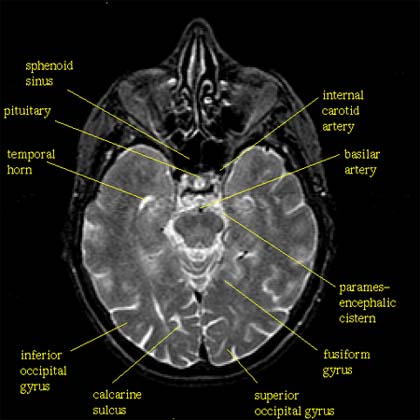

Les régions du cortex spécialisées dans le traitement des couleurs, des graphèmes (lettres et chiffres), des quantités et des informations relatives à la localisation spatiale sont repérées. Les deux premières sont localisées dans une région corticale appelée gyrus fusiforme.

Image Localisation du gyrus fusiforme par jauzein, mis à jour le 27/10/2015 13:53

L'image IRM en coupe permet de localiser le gyrus fusiforme dont la lésion est mise en cause dans la prosopagnosie.

Image IRM témoin prosopagnosie par jauzein, mis à jour le 27/10/2015 13:53

L'image montre l'aspect de la coupe, dépourvue de lésion, chez un individu témoin.